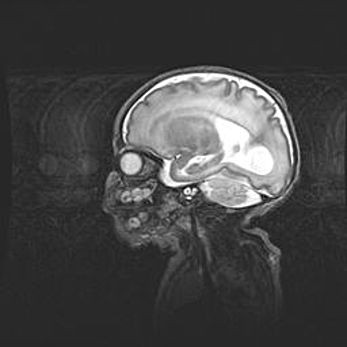

Церебральная ишемия II.

Возраст: 5 дней

Вес: 3400 г

Пол: женский

Окружность головы: 35 см

Срок гестации: 39 недель

Церебральная ишемия – это заболевание, характеризующееся недостаточностью (гипоксией) либо полным прекращением (аноксией) снабжения мозга кислородом по причине закупорки одного или нескольких сосудов. Это приводит к  что метаболическим расстройствам различной степени тяжести в тканях головного мозга, развитию коагуляционных некрозов и гибели нейронов.